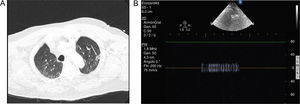

We present a case of massive pulmonary embolism with pulmonary infarction. The patient was on mechanical ventilation due to right heart failure and severe hypoxemia. Pulmonary CT showed in the lung parenchyma an area of triangular morphology in peripheral location with increased density and frosted glass appearance compatible with pulmonary infarction on the left upper lobe (Fig. 1, Panel A, arrow). Over the same location, central bronchial reflex is seen as an hyperechoic structure surrounded by hypoechoic tissue on ultrasound exam. Bronchus can be identified by pulsed-Doppler, showing the flow of gas insufflated by ventilator (Fig. 1, Panel B).